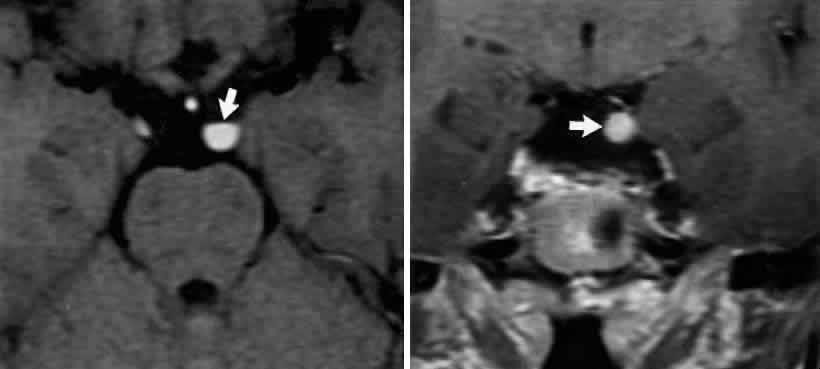

FASCICULAR LESIONS Deficits of the oculomotor fasciculus are usually identified by the accompanying brain stem signs. Oculomotor palsy with contralateral hemiplegia (Weber syndrome) indicates involvement of the corticospinal tracts. Contralateral ataxia and intention tremor (Benedikt syndrome) indicates involvement of the red nucleus (see Fig. 2). Nothnagel syndrome is an eponym given when signs of both Weber and Benedikt syndromes are present. Midbrain vascular accidents account for most fascicular defects. Ksiazek84 shed some light on the fascicular arrangement of the oculomotor nerve based on two patients with partial oculomotor paresis, each with pupillary mydriasis, significant inferior rectus paresis, and medial rectus paresis. Neuroimaging revealed a lesion in the fascicular portion of the nerve, thus indicating the proximity of these fibers in the fasciculus. Monocular elevator paresis (superior rectus and inferior oblique) in mass compression of the oculomotor fasciculus has also been reported.85 In this regard, Castro and associates86 proposed the mediolateral somatotopy of the oculomotor fascicular fibers within the mesencephalon with the inferior oblique and superior rectus muscles being most lateral, and the pupilloconstrictor fibers and inferior rectus being most medial. The levator palpebrae fascicles are in an intermediate location between the superior rectus and medial rectus fascicles. INTERPEDUNCULAR LESIONS Basal lesions, including the rare rostral basilar artery aneurysm, may encroach on the oculomotor nerves as they exit in the interpeduncular space. Such slow-growing aneurysms, either saccular or fusiform, may present as partial oculomotor palsies with or without involvement of pyramidal tracts, and without subarachnoid hemorrhage.87 Aneurysms of the posterior communicating artery, on the other hand, are probably the most common lesions causing acute spontaneous oculomotor palsies (Fig. 12). According to Hyland and Barnett,88 the oculomotor palsy that occurs with posterior communicating aneurysm is not necessarily due to mass effect per se, but rather is attributed to hemorrhage that suddenly enlarges the aneurysmal sac to which the oculomotor nerve is adherent, or to hemorrhage into the substance of the nerve itself. Most patients present, therefore, with an intensely painful, complete unilateral oculomotor palsy in association with other signs and symptoms of subarachnoid hemorrhage. Few patients with symptomatic posterior communicating aneurysms are found in office waiting rooms: they are usually obtunded or comatose in emergency rooms. Involvement of pupillary fibers is such a consistent finding in third nerve palsies due to bleeding aneurysms that most clinicians concur in this useful dictum: a pupil-sparing, but otherwise complete, third nerve palsy is very unlikely to be due to posterior communicating aneurysms. Careful pupil evaluation may disclose subtle abnormalities in “apparent pupil-sparing,” especially in cases of aberrant regeneration or with chronic cavernous sinus lesions. Generally, in patients at least 50 years of age or older, an acute, isolated, painful oculomotor palsy that spares the pupil is caused by intraneural ischemia; nevertheless, these patients must be carefully observed for further evolution. In our opinion, an acute complete oculomotor palsy with moderate to major mydriasis, even when diabetes is present, is an indication for cerebral arteriography. It should be emphasized that magnetic resonance angiography may not detect aneurysms smaller than 3 to 4 mm.89 The clinical management of patients with relative pupil-sparing third nerve palsies remains in debate. Observation alone arguably is appropriate management of such patients; however, since practically every conceivable combination of partial ophthalmoplegia and pupillary abnormality has been reported in aneurysmal compression of the third nerve, it is better to err on the side of caution and perform angiography more frequently. It is incumbent upon the physician to evaluate carefully the proportion of ophthalmoplegia and ptosis in relation to the degree of pupillary abnormality when deciding appropriate workup of these patients. Again, the increasing sensitivity of magnetic resonance angiography has not yet entirely replaced formal angiography. Certainly, neurosurgical intervention requires conventional cerebral arteriography before surgical treatment. Capó and colleagues90 pointed out that the interval from onset to maximal ophthalmoplegia does not differentiate between microvascular (3.3 days) and aneurysm (3 days), but that failure to recover within 4 to 8 weeks requires further evaluation. Other partial oculomotor palsies occur regularly with cavernous sinus masses and parasellar syndromes (see below), accompanied by variable pupillary findings. Furthermore, both acute and chronic lesions may produce incomplete palsy of the superior division (supplying levator palpebrae and superior rectus muscles) or of the inferior division (medial and inferior recti, inferior oblique and pupillomotor fibers). If pain or first trigeminal division numbness are absent, and if the pupil is uninvolved, such fractional oculomotor pareses are regularly misinterpreted as myasthenia or local orbital inflammations. Guy et al91 described five patients with isolated ptosis and elevator paresis in abduction, consistent with selective “superior division” involvement. They also discussed five previously reported cases with the following respective diagnoses: (1) intracavernous aneurysm (usually with associated Horner's syndrome) and basilar artery aneurysm; (2) diabetic ophthalmoplegia; (3) meningitis; (4) dural lymphoma; and (5) postsurgical manipulation of parasellar structures. In essence, there was little anatomic correlation with the physical separation into superior and inferior oculomotor trunks that occurs in the cavernous sinus. Moreover, two patients sustained superior division palsies during surgical manipulation of the subarachnoidal portion of the oculomotor nerve trunk. A number of cases of inferior rectus paresis, isolated or in combination with ipsilateral or contralateral superior rectus paresis, have been construed as focal lesions involving the rostral portion of the oculomotor nuclear complex.80–82 Oculomotor palsy following head trauma is not rare, but probably occurs less frequently than traumatic fourth nerve palsies. As a rule, such closed-head injury causes loss of consciousness and is accompanied by skull fracture, but this is not invariable. Injury to the ocular motor nerves in road accidents was studied by Heinze,92 who dissected the cadavers of 21 fatal cases. He found that the relationship of frontal or temporal fractures to neural damage was unpredictable. In fact, intact nerves were encountered adjacent to gross fracture sites. The oculomotor nerve was damaged at three locations: (1) avulsion of the rootlets at their ventral exit from the brain stem; (2) contusion necrosis of the most proximal portion of the nerve trunk; and (3) intraneural and perineural hemorrhage of the nerve trunks at the level of the superior orbital fissure. Of great interest are Heinze's findings of focal hemorrhages in extraocular muscles, usually associated with fractured orbital bones. Eyster et al93 reported three patients with large basicranial tumors, who presented with oculomotor palsies precipitated by mild blows to the head that were insufficient to cause fracture or loss of consciousness. The oculomotor nerves were encased and stretched by tumor, which apparently rendered these tethered nerves vulnerable when innocent head blows abruptly shifted the brain. The authors pointed out that such atypical presentations of intracranial tumors may further mimic aneurysms, since subarachnoid hemorrhage does occasionally occur with tumors. Neetens94 reported an additional three cases of oculomotor nerve palsies after minor trauma in the presence of basal intracranial tumors; the trochlear nerve was involved in all three cases, and in two cases the oculomotor nerve was partially affected. Walter et al95 reported two instances of minor head trauma resulting in complete third nerve palsies attributed to occult posterior communicating artery aneurysms. We have seen a 45-year-old school teacher who experienced an immediate right abducens palsy when playfully slapped on the back of the head; within weeks, other cranial nerve palsies announced the presence of diffuse meningeal spread of carcinoma. In the United States, basilar meningitis is rare, but was formerly encountered with tuberculosis and syphilis. When the third nerve is involved in such cases, progressive defects are the rule and other cranial nerve palsies are commonly found. Oculomotor palsy may especially occur with meningitides in infants, including instances of viral and bacterial (e.g., Streptococcus pneumoniae, Haemophilus influenzae) infections.96 Oculomotor nerve compression by the proximal segment of the posterior cerebral artery, or by the uncus against the petroclinoid ligament, can be seen with increasing cerebral edema or with an ipsilateral expanding supratentorial mass, and it is often heralded by unilateral pupillary dilation (Hutchinson pupil). Progression rapidly leads to complete ocular motor nerve palsy. Keane97 reviewed the ocular motor signs of tentorial herniation, which include anisocoria and parasympathetic pupillary abnormalities, unilateral or bilateral ptosis, internuclear ophthalmoplegia, vertical gaze paresis, and partial third nerve palsies. CAVERNOUS SINUS LESIONS The oculomotor nerve may be involved by inflammatory disease, tumor, aneurysm, arteriovenous fistula, or thrombosis at the level of the cavernous sinus. The third nerve is usually involved in combination with the fourth, sixth, and ophthalmictrigeminal nerves, and accompanying sympathetic paresis may minimize pupillary dilation. The syndrome of the cavernous sinus, therefore, includes multiple ocular motor nerve palsies and pain or numbness in the first trigeminal division. In practice, lesions involving primarily the superior orbital fissure produce signs and symptoms that, with the possible exception of proptosis, cannot be distinguished from those of the anterior cavernous sinus. In particular, dural carotid cavernous fistulas that drain primarily into the inferior petrosal sinus may cause third nerve pareses without significant orbital congestion.98 Third nerve palsies due to lesions in the cavernous sinus tend to be partial in that all muscles innervated by the oculomotor branches need not be involved. This is especially true of pupillomotor fibers, such that the pupil may be normal or minimally involved. This “pupil- sparing” is offhandedly attributed to the superimposition of sympathetic paresis (Horner syndrome), but appropriate pharmacologic tests rarely substantiate this explanation (see below, Parasellar Syndrome). More likely, slowly expanding masses (e.g., infraclinoid aneurysm, meningioma) functionally spare the pupilloconstrictor fibers in the intracavernous portion of the oculomotor nerve. In addition, the levator, superior, inferior, and medial recti may be involved in unequal degrees, but progressive paresis evolves. (Once again, myasthenia must be suspected in any nonpainful, pupil-sparing, nonproptotic ophthalmoplegia, with or without ptosis.) Cavernous sinus lesions are further discussed below. Primary neurinoma of the oculomotor nerve is a relatively rare lesion that should be considered in children or young adults with insidious third nerve palsy. These may occur in the cavernous or interpeduncular portion of the nerve (Fig. 13).99,100